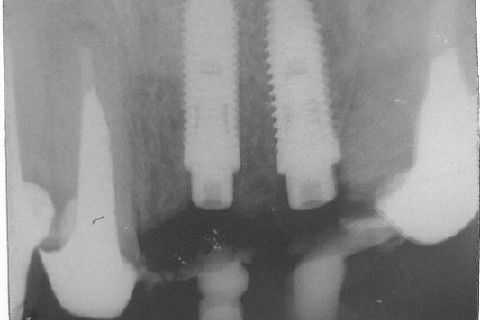

Cirurgia realizada hoje de manhã...No planejamento percebi medindo espessura do rebordo com especímetro que as medidas não estavam muito boas, ou o ideal, em torno de 4,5 a 5 mm ate´o terço médio do rebordo e melhorava no final, com 6 a 7 mm. Optei então por uma pequena expansão usando os expansores rosqueáveis. Aconteceu uma pequena fenestração na hora da fixação dos implantes, especialmente na região do 22 que fraturou o início da tábua óssea, mas não me preocupei porque não foi mais do que 2 mm de fratura em direção apical, o implante ficou infraósseo e com boa estabilidade (60 N no 21 e 40 N no 22). Esta fratura tb não deixou osso completamente solto, foi do tipo galho verde, deixei em posição e suturei normalmente. Só não fiz e nem estava planejado carga imediata mesmo, mais pelo motivo da oclusão inadequada do caso.